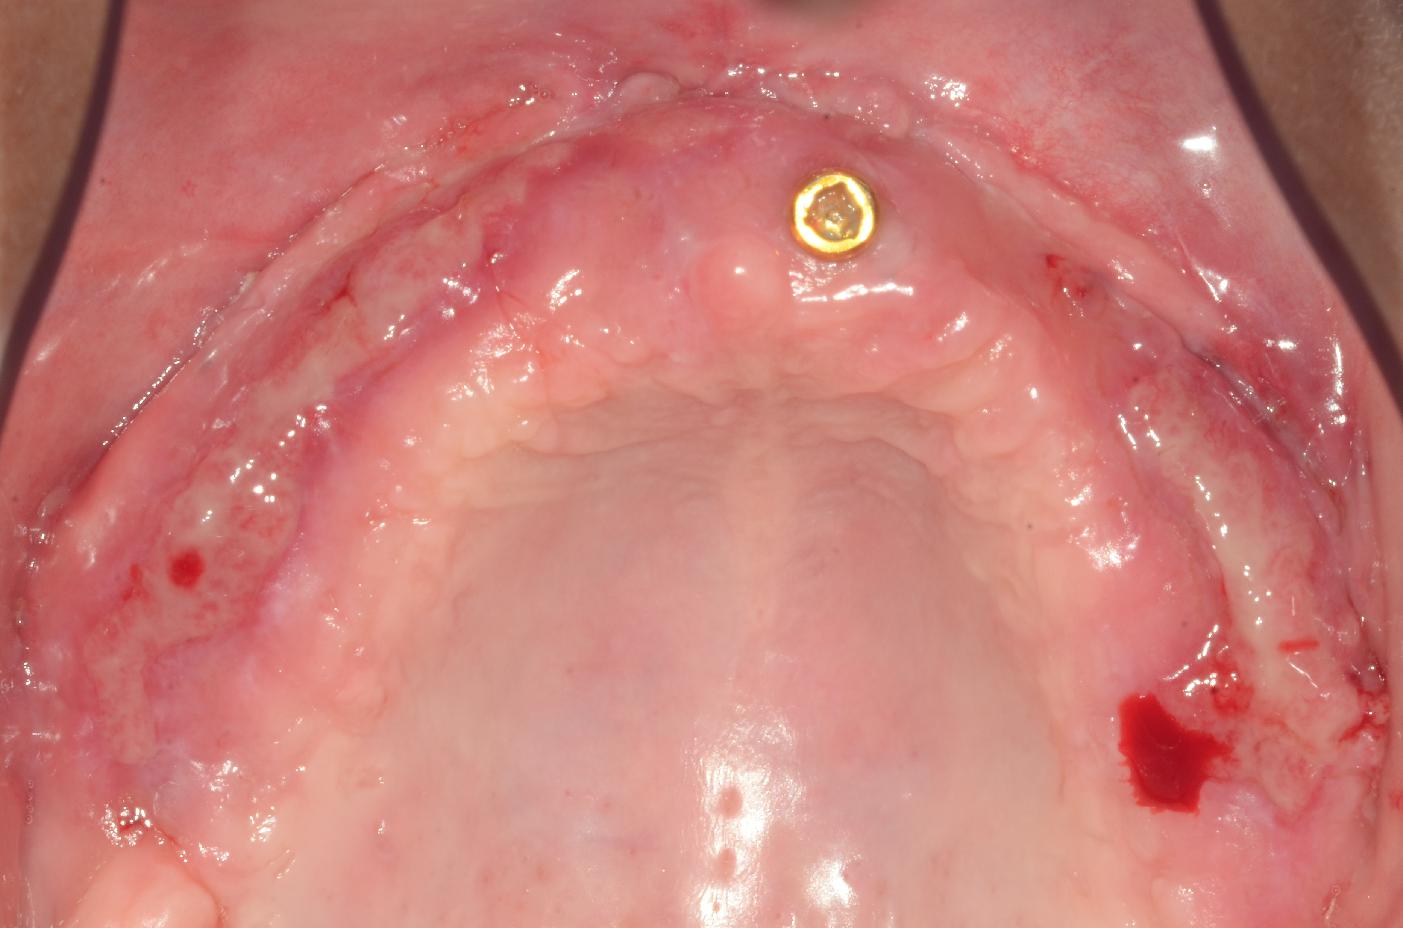

8/8 - Post-operative healing at 6 months with excellent tissue maturation and favourable color and thicknessmucoderm® for full arch reconstruction of insufficient vestibular depth and lack of keratinized tissues - Dr. B. Mólnar & Prof. P. Windisch